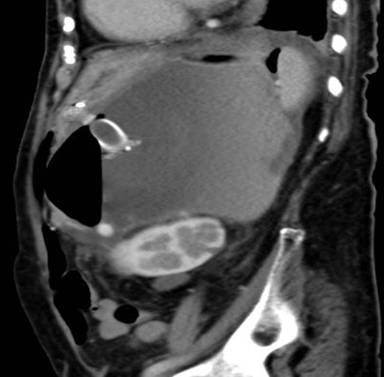

Three weeks later, she presented again with vomiting. EGD revealed that the stent had migrated into the stomach. This was subsequently removed and a larger diameter stent was inserted into the original tract, a Niti-STM Biliary Stent (NAGITM) (Taewoong-Medical Co, Seoul, South Korea), 16 mm in diameter x 30 mm in length. She was carefully followed up and nine months post procedure remained well. Her appetite was good and her abdominal discomfort had resolved. A recent repeat CT scan (Figure 6) showed that the stent was still in situ and the cyst had completely collapsed.

Figure 6. CT abdomen after 6 months of stent insertion showing stent in-situ and resolution of lesion. |